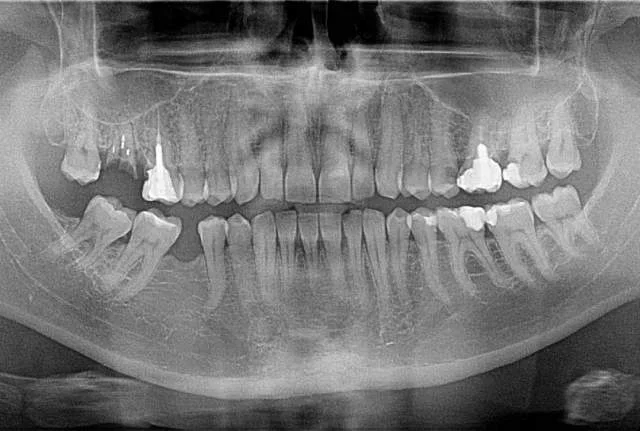

Shitet grafi dentare panoramex dhe cefalometri sirona xg 3d. Prodhim i vitit 2016 . Nje vit garanci Cel. : 0683869777

Shitet Panorameks 2D/2D+ Carestream (Kodak) Aparati është në gjendje shumë të mirë si nga ana vizuale dhe nga ajo funksionale. Ka edhe opsionin...